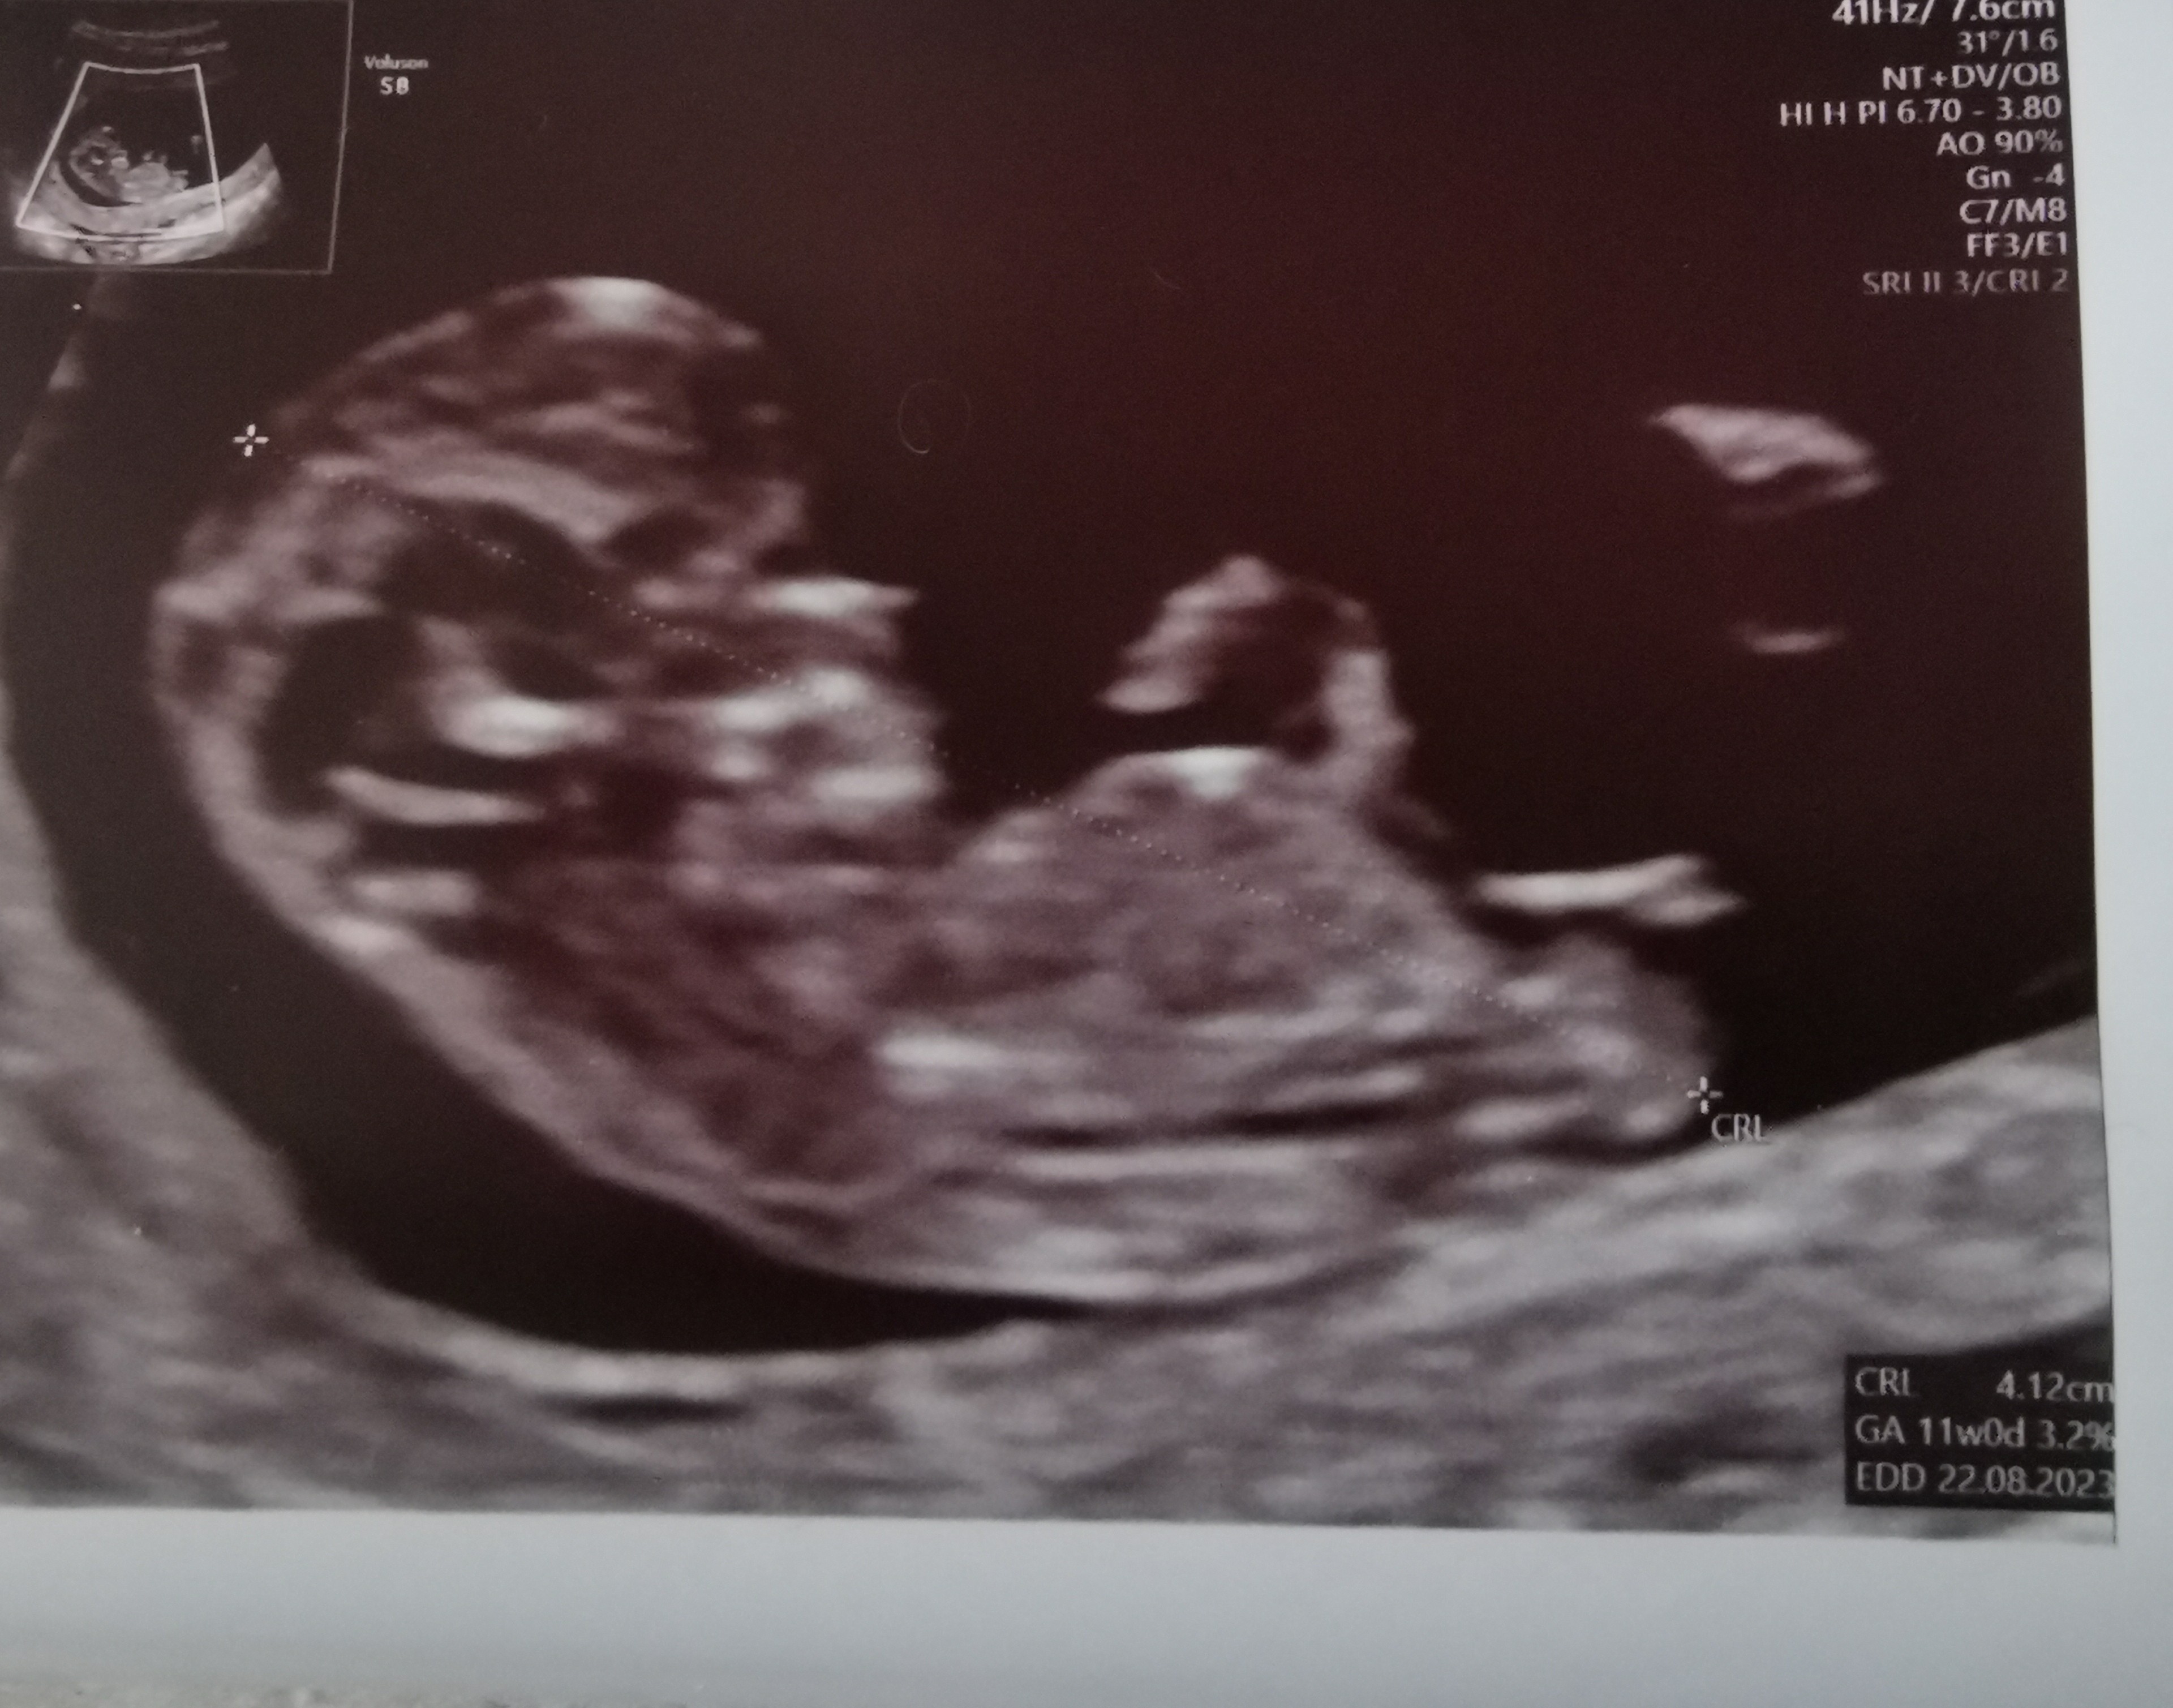

Dziewczyny czy coś tu widać? Chłopczyk & dziewczynka?

Byłam u lekarza natomiast nie pytałam o płeć myślałam ze to zdecydowanie za wcześnie ale czytając niektóre posty dziewczyny się dowiadywały w 13 tyg 🙈

• IMG_20230314_094512.jpg

1,3 MB · Wyświetleń: 683

Jakby lekarz cos widzial i mial pewnosc to by cos sam powiedzial. Jestes w 11+0 to moze byc jeszcze troche za wczesnie na okreslanie plci na podstawie wygladu wyrostka plciowego.